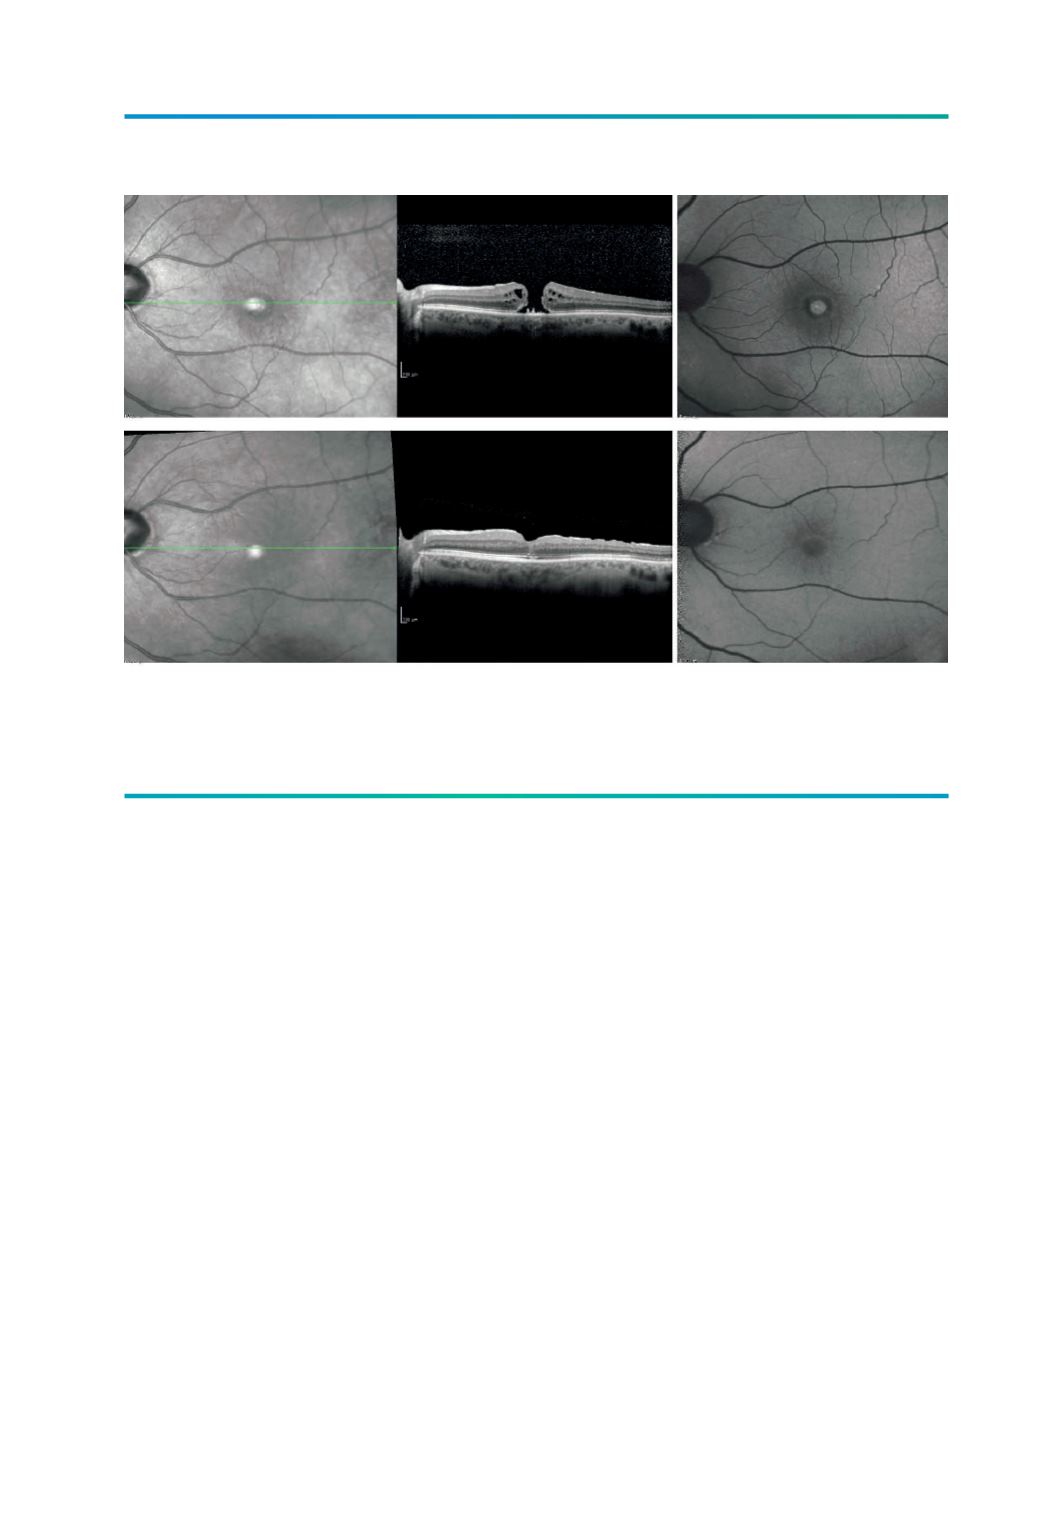

Figura 4.

A e B) Avaliação pré operatória de doente com BM, com hiperAF central e halo hipoAF circundante.

C e D) Avaliação pós-operatória evidenciando no OCT um encerramento do BM com normalização da

autofluorescência e melhoria da AV para 7/10.